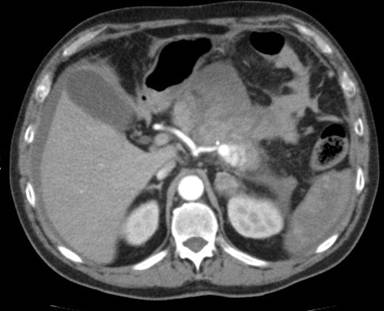

Figure 1. CT scan with arterial phase with a bleeding pseudoaneurysm. |

Case #5 with pseudoaneurysm arising from splenic artery, experienced spleen abscesses after embolization (Figure 1). It was managed successfully only with conservative treatment (Table 1).